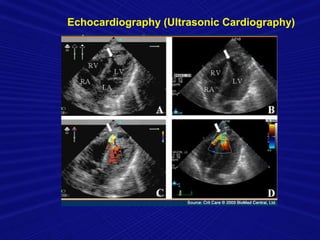

Echocardiography (Ultrasonic Cardiography)

• #26 Based on the symptoms, a doctor may suspect pulmonary hypertension in people who have an underlying lung disorder. A chest x-ray may show that the pulmonary arteries are enlarged.